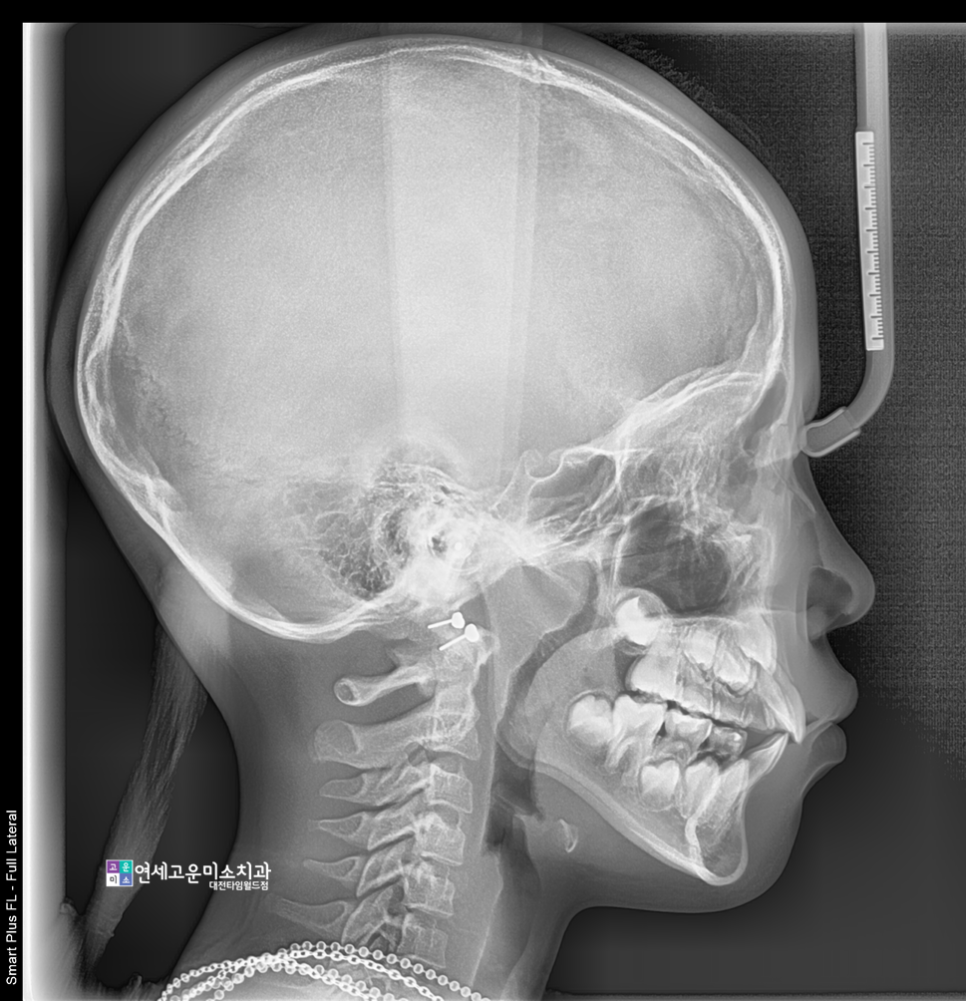

옆에서 찍은 엑스레이를 볼 때

윗니와 아랫니 앞뒤 차이가

크게 난다는 점을 알 수 있습니다.

많이 줄어든 것이 확인됩니다.

정말 많이 감소했습니다.